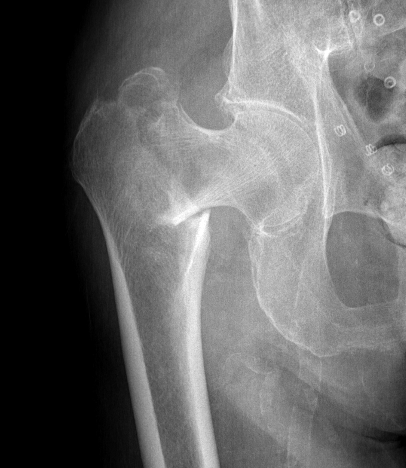

Malunion

Excessive lateral sliding / shaft medialisation

Cause

- collapse with insufficent lateral buttress

- reverse obliquity fracture

Management

1. Fracture united

- remove screw

2. Fracture non union

- revise fixation in young patient

- hemiarthroplasty / THA